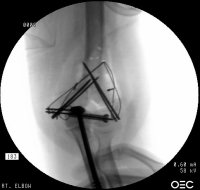

Initial fixation:

Click for larger image